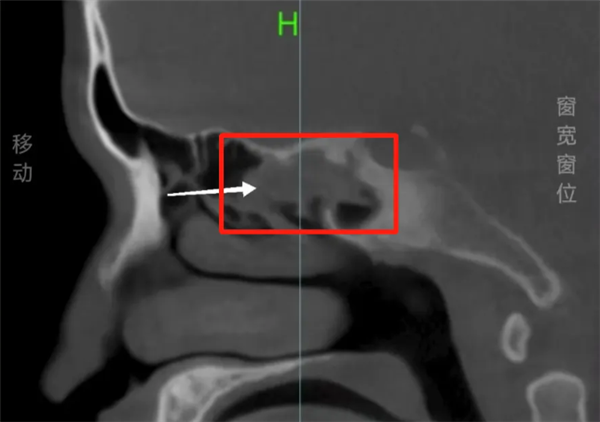

医生凭借经验,跳过鼻内镜直接建议CT检查,结果发现他的右侧蝶窦存在占位性病变,初步怀疑是“骨瘤”,同时伴有右上颌窦囊肿、筛窦炎、蝶窦炎、鼻中隔偏曲及鼻炎。

医生表示,这个异物不一定是骨瘤,但长期存在已导致慢性炎症和反复头痛,必须手术探查。

术中,医生从阿杰的右侧后组筛窦取出的竟是一截长约3厘米、质地坚硬的树枝。